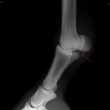

Čip ve spěnkovém kloubu na pánevní končetině

Ankylóza spěnkovýho kloubu

rentgenologické vyšetření

ohebové zkoušky